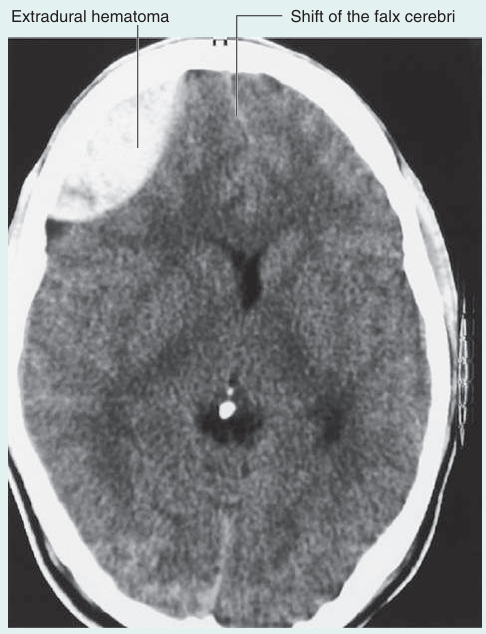

1) 경막바깥출혈, 경막밑출혈: 주로 외상과 관련

분류

출혈 발생 위치

주된 발생 원인

특징

영상

경막외혈종

두개골과 경막 사이

두개골 골절

주로 압력 높은 arterial 혈종

경막이 혈종의 압력을 막는 방패 역할을 하면서 뇌실질은 거의 손상되지 않고, 예후가 좋다.

렌즈 모양 출혈